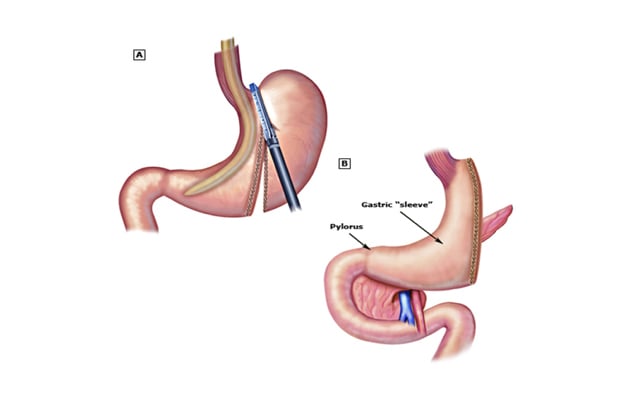

Sleeve gastrectomy

Sleeve gastrectomy

A: Stapling of the greater curvature of the stomach in sleeve gastrectomy. B: Completed sleeve gastrectomy.